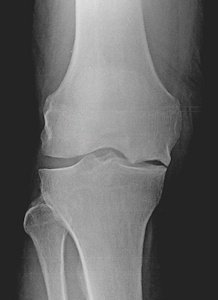

Kısmi (parsiyel, unikondiler) diz protezleri, aşınmış olan diz ekleminin sadece bir kısmının protez ile yüzey kaplanmasının yapıldığı protezlerdir (Resim 1).Resim 1a,b: Total ve unikondiler diz protezi arasındaki fark.